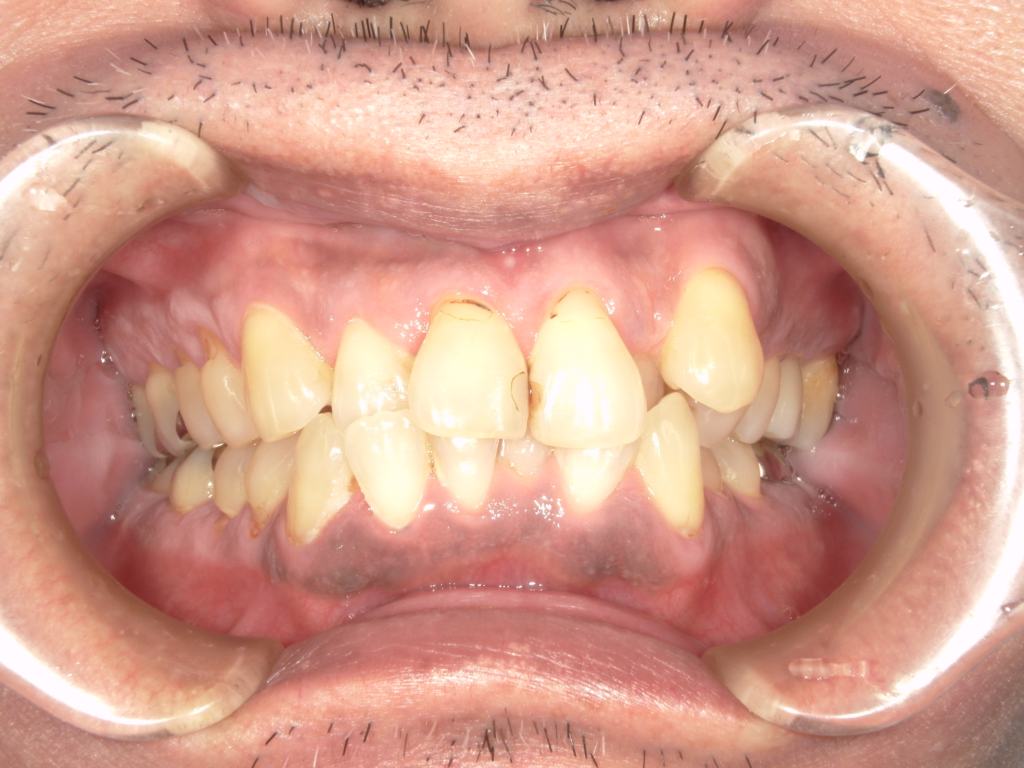

前歯の4本が、残すのが難しい状況となり、インプラント治療を行いました。

インプラントは前歯に2本埋入し、4本の前歯を作っています。歯を抜くと同時にインプラントを埋入し、仮歯を作りました。その後2ヶ月で、被せ物を入れました。被せ物は、セラミックスで作っています。

治療前

治療後